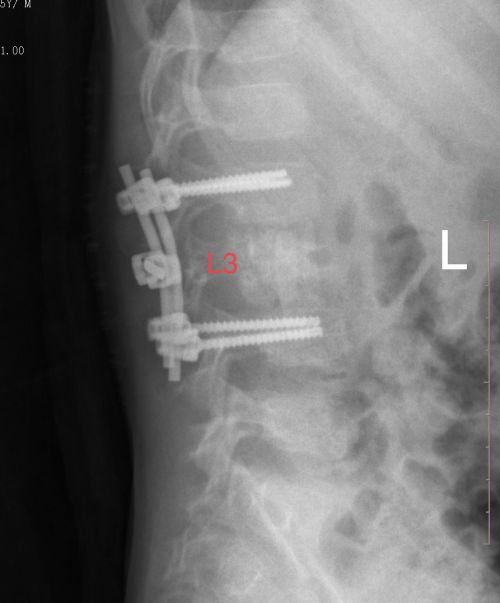

术后X线显示:L2-L4椎体内固定,L3植骨充盈。

考虑到康康腰椎病变进展迅速,且出现神经压迫症状,病变范围较大、位置较深,仅行常规腰椎后路手术难以彻底刮除病变组织,肖晟主任组织科内讨论并邀请小儿泌尿外科专家会诊后,决定由小儿骨科肖晟主任医师、文捷博士与小儿泌尿外科郭玺副主任医师联合施行前路腰3病变切除活检植骨+后路L2-4脊柱植骨融合内固定术。

术中,三位大咖完美配合,避免了肾脏等腹部深层脏器的损伤,从腰腹部前入路彻底刮除椎体肿瘤,并填充植骨得以恢复椎体高度,避免了椎体进一步压缩骨折及神经功能损伤。手术历时3个小时圆满完成,出血不到100ml。病理结果证实为“腰椎朗格罕细胞组织细胞增生症”。